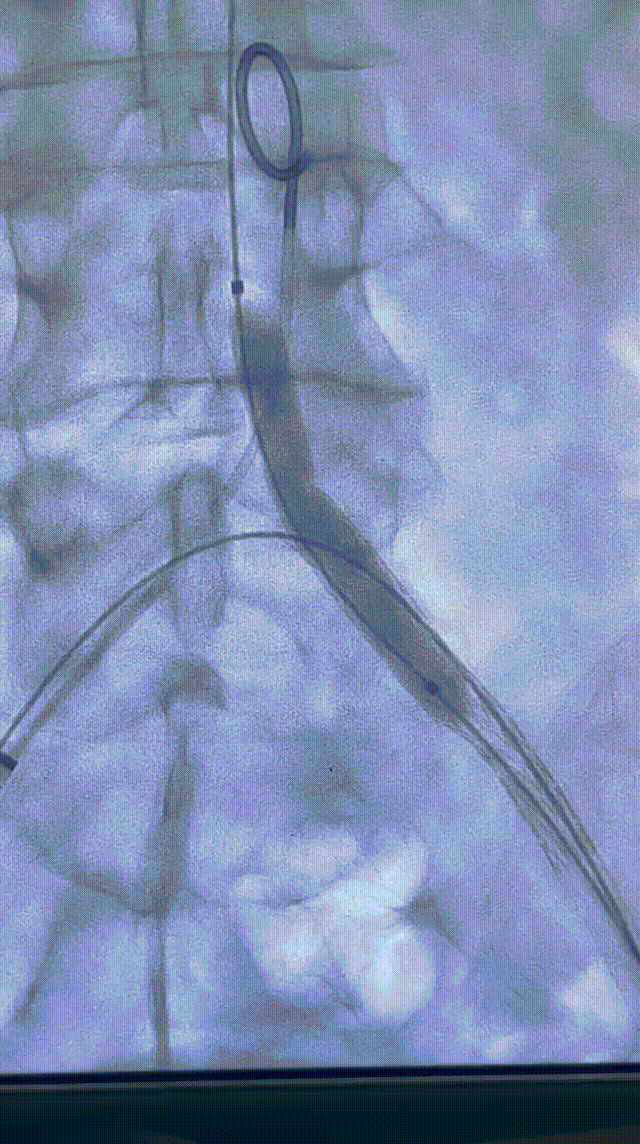

预扩后造影显示管腔打开。导入8F长鞘,通过长鞘输送并植入6X100mm 的VIABAHN 支架。继续通过8F长鞘导入VBX 支架,VBX支架近端定位在髂总动脉开口处,远端重叠在VIABAHN 支架内25mm左右。通过长鞘造影判断VBX支架位置后开始释放支架。根据产品外包装提示,当压力泵压力在6atm时,VBX 支架直径为7.1mm,此时支架会完全展开。故第一次加压6atm,支架顺利展开后排空并回撤球囊。调整球囊位置避开支架重叠区,在髂总动脉开口处再次给球囊加压到11atm,观察到支架直径随球囊的增大发生了扩张。根据产品信息提示此时已到达目标直径8mm。撤出球囊后在腹主动脉做整体造影,髂动脉开通良好。但发现VBX 支架近端与左侧腹主动脉分叉处贴壁不完全,判断是由于球囊后扩张是翻山的形式,使支架跟随了球囊的形态导致,故左侧股动脉入路上8mm直径的球囊在VBX开口处进行贴壁性后扩。支架形态被成功纠正,贴壁良好。

释放6x100mm VIABAHN 支架

导入VBX 支架

6atm压力释放

释放VBX支架,11atm的压力

8mm*6cm P3球囊

术后造影结果

术后造影显示,支架呈现8mm-7mm-6mm的梯度锥形,管腔打开完全,定位精准,贴壁良好。

术后造影